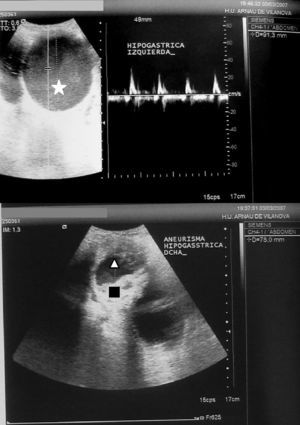

La radiografía de tórax no permitió detectar signos de insuficiencia cardíaca ni cardiomegalia. El electrocardiograma mostró ritmo sinusal a 72lpm, sin criterios de crecimiento ventricular. Las pruebas analíticas realizadas, incluyendo la de función renal, fueron normales. Se practicó una eco-Doppler abdominal y de miembros inferiores, que demostró permeabilidad del sistema venoso, con ausencia de trombosis venosa profunda asociada. Se observó la presencia de aneurisma en ambas arterias ilíacas internas (derecha: 6cm, izquierda: 9cm), sin evidencia de rotura aguda. La aorta era de calibre normal (fig. 1). La tomografía axial computarizada (TAC) realizada confirmó los hallazgos de la eco-Doppler (fig. 2).